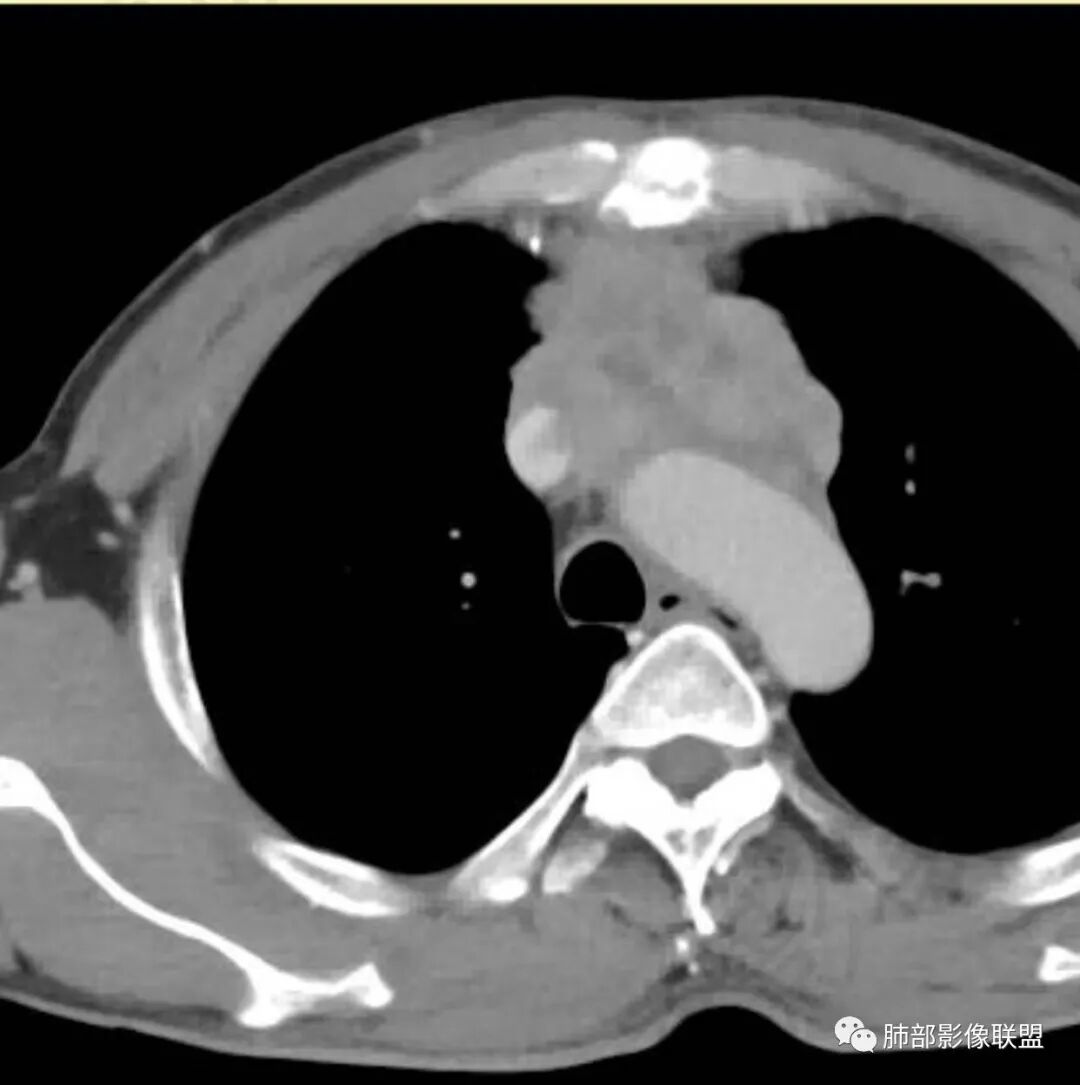

2.影像表现:前上纵隔较大肿块,密度不均,形态不规则,边界不清,有结节样突起,脂肪间隙显示不清。病灶侵犯左无名静脉及上腔静脉,其中左无名静脉闭塞(胸背部侧支循环明显,亦表明回流受阻)。增强后轻中度不均强化。坏死边界欠清晰。可见心包积液,提示心包受侵犯。右侧上叶及纵隔胸膜下结节影,疑胸膜肺转移可能。胸骨柄后缘皮质不完整,疑骨质破坏(未提供骨窗及矢状位图像)。左锁骨上可见肿大淋巴结。

胸腺癌:病灶边界不清,骨骼及血管受侵破坏,胸膜、肺及心包受侵转移等首先想到胸腺癌。胸腺癌最常见病理类型为鳞癌,占70-79%。预后较差,50-65%初诊时伴肺转移,极少伴重症肌无力。影像:胸腺鳞癌形态不规则,易坏死,范围大,坏死区边缘常模糊。

淋巴瘤:体积常较大,常见常在10cm以上,相对低密度结节样堆砌感比较明显,对待骨骼、血管等结构相对“温和”,所谓“血管漂浮”、“肉包骨”则较为常见。病理类型几乎只见于:经典HD、大B细胞淋巴瘤,前驱T淋巴母细胞瘤。实验室检查LDH可升高。初诊时罕见钙化,罕见胸膜受侵。有坏死也常常边界清楚或呈囊变样外观,可伴纵隔、锁骨上淋巴结肿大。